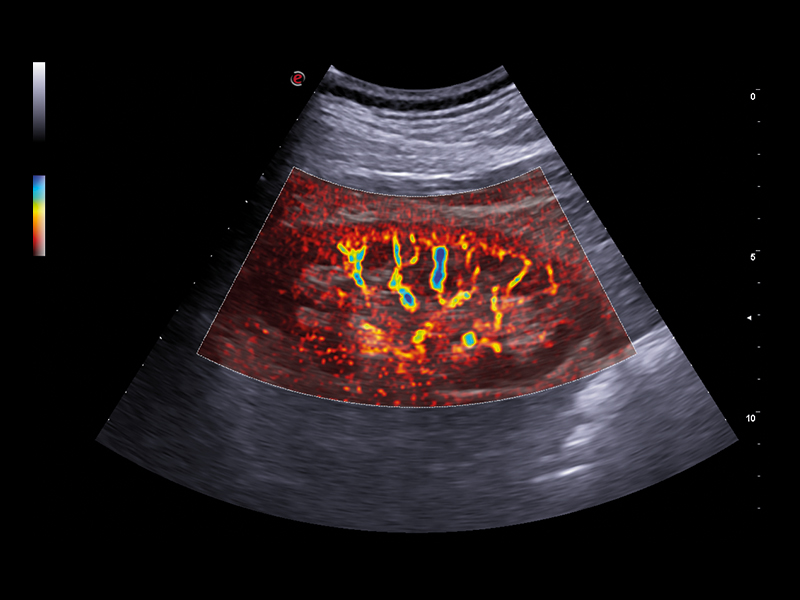

• CnTI™ Clear (Contrast Tuned Imaging): Contrast Enhanced Ultrasound (CEUS) Imaging of Esaote, CnTI™ Clear, detects organ perfusion through contrast agent enhancement to support liver and abdominal lesion characterisations. Based on cutting-edge software, CnTI™ Clear is able to detect low levels of microbubbles, especially in the early arterial phase, while it will ensure their longevity, to give you accurate information on how the lesion is reacting.

• Q-Pack: additionally, Q-Pack is an advanced feature that monitors and quantifies, in graph form and as a function of time, the hemodynamic information detected within a selected ROI, using methods such as CEUS or Doppler Mode.